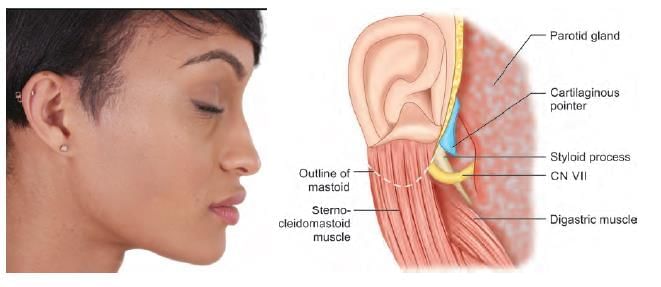

NOT an anatomical landmark of facial nerve identification in parotid surgery: (NEET-PG 2020p)